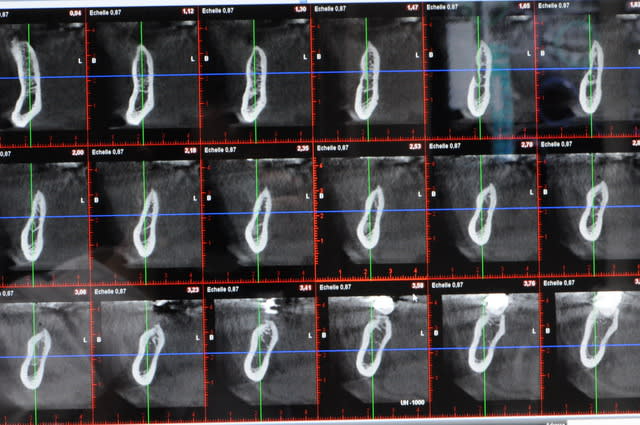

je post les coupes des que possible

J’ai une tranchée finale qui fait 8 à 9 mm moins 1 mm du trait de coupe donc il faudrait une triangulation pour le calcul mais je verrais les coupes scan une fois solidifié c’est + simple)

Merci pour la planification 3D, ça aide beaucoup à suivre ton cas. c'est quoi ton logiciel ?